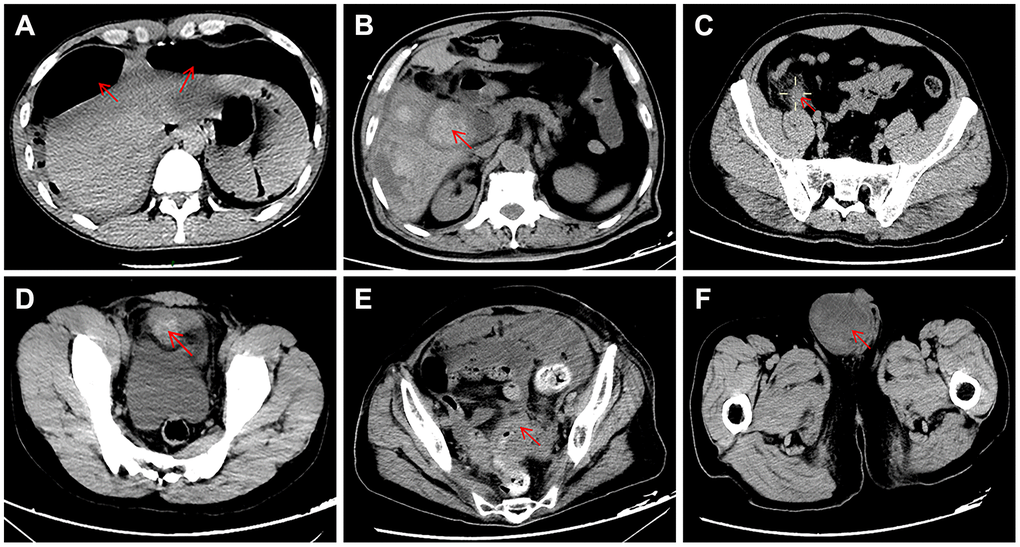

Of the 28 patients who did not have COVID-19 pneumonia (9 female and 19 male; mean age 55 years (range 17–87)), 12 (43%) patients were diagnosed with acute appendicitis, 10 (36%) with gastrointestinal perforation, 5 (18%) with intestinal obstruction and 1 (4%) with bladder rupture. The typical abdominal CT appearance is shown in Figure 1. Comorbidities were found in 17 (61%) patients and included diabetes mellitus in 7 (25%), coronary heart disease in 7 (25%), hypertension in 6 (21.4%), chronic obstructive pulmonary disease in 2 (7.1%), chronic renal failure in 1 (3.6%), chronic liver failure in 1 (3.6%), acute myeloid leukemia in 1 (3.6%), and rheumatoid arthritis in 1 (3.6%). Five (17.9%) patients were reported to have postoperative complications: one had intra-abdominal infection, one had a wound infection, and three had multiple organ dysfunction syndrome (MODS). All three patients with postoperative MODS had preoperative comorbidities (case 1: coronary heart disease and chronic renal failure; case 2: chronic liver failure; case 3: hypertension and coronary heart disease). In total, 25 (89.3%) patients were cured, and the remaining 3 patients died due to severe septic shock and MODS.

Figure 1. Typical appearance of abdominal CT showing the causes of acute abdomen in the present study. (A) duodenal perforation accompanied by free intraperitoneal gas; (B) gangrenous cholecystitis; (C) acute appendicitis; (D) bladder rupture; (E) intestinal obstruction caused by carcinomas in the rectosigmoid junction; (F) intestinal obstruction caused by inguinal incarcerated hernia.